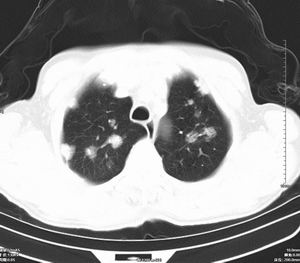

男 60岁,咳嗽,胸疼半年,请各位老师讨论.

肺内多发小结节,部分内见空泡,边界大部分清楚.多考虑:1 韦格氏肉芽肿.2 肺泡癌伴肺内转移不除外.

肺内多发结节样病灶,部分内见空泡影,边界大部分清楚,多考虑:

1.金葡菌感染

2 转移不除外

肺内多发小结节,部分内见空泡,边界大部分清楚.多考虑:1 韦格氏肉芽肿。

影像学表现:文献报告肺部浸润性见于50-65%的病人,肺部均有浸润,表现为肺内多发或单发结节影,出现多发厚壁空洞,内壁粗糙,易合并细菌性肺炎,也可出现胸腔积液。ct及hrct扫描可见大小不等的结节多分布于肺周边部,结节可呈楔形贴近胸膜,另一主要特征是其周围有线状斑痕影,即长毛刺征,受累血管及血管周围纤维化是其形成的原因,如累及胸膜尚可出现胸膜凹陷征。71%ct比胸片发现更多更小病灶, 典型的征象滋养血管征仅能在ct上显示。ct及hrct可检出典型影像征象。为诊断提供了重要依据,ct可成为肺韦格氏肉芽肿首选检查方法。

鉴别诊断:韦格氏肉芽肿ct表现与肺有关病变相似。如脓毒性肺栓塞的ct表现包括多发性,并有滋养血管的空洞性结节。滋养血管征也常见于肺梗塞和血行转移瘤。另外部灶呈楔形贴附胸膜面也是梗塞和脓毒性肺栓塞的ct特点之一。但肺梗塞和脓毒性肺梗塞的临床表现较急、全身或局部症状明显,另外肺结节边缘长毛刺征及胸膜凹陷征是上述病变所缺乏的,有助于本病的诊断和鉴别诊断。所以本病例应考虑肺转移。